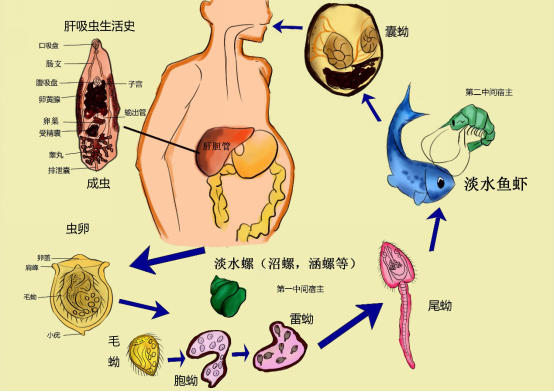

二等奖作品(3):肝吸虫的“四季” 作者:19护理学 吴梓豪